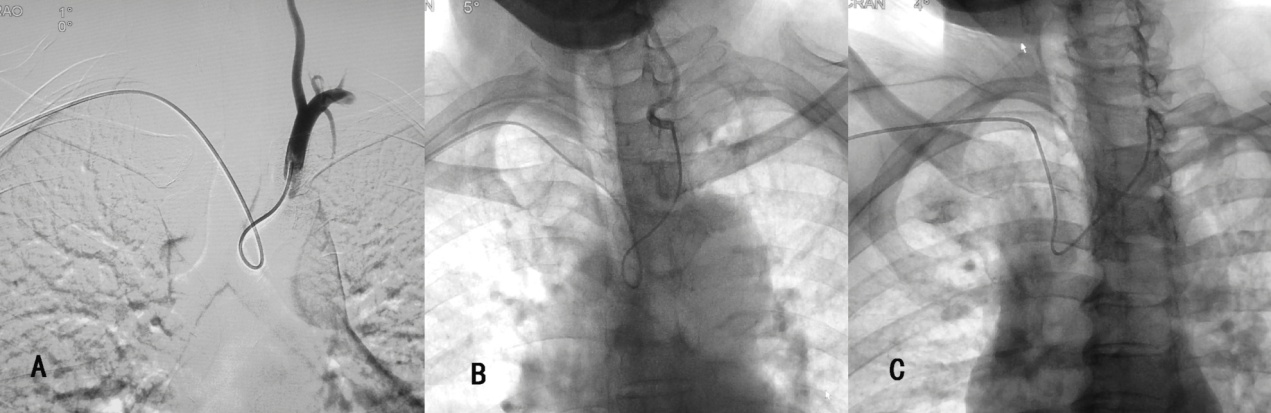

因此, 需使用西蒙管的反勾技术(使导管扭曲呈“8”字形而不是导管原塑性的形状,使得导管末端的方向朝上)才能实现血管的超选(图5),这造成导管的操作困难